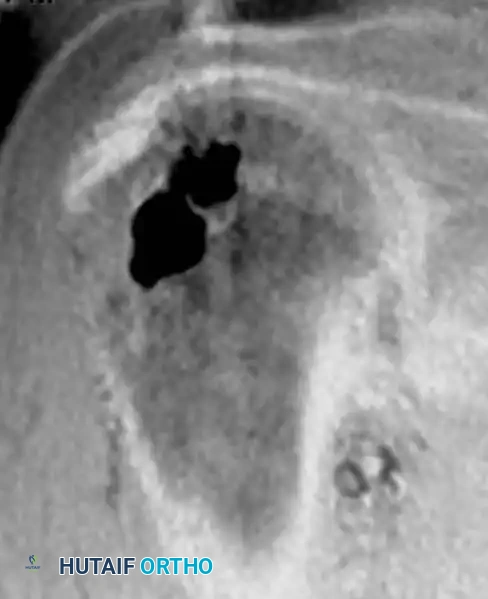

The diagnosis is almost exclusively made via plain radiography and MRI. Radiographically, bone infarcts present as well-defined metaphyseal or diaphyseal lesions with irregular, serpiginous borders.

Fig. 20-23: (A and B) Plain radiographs demonstrating irregular, serpiginous calcification in the metaphysis of the distal femur in a 50-year-old woman with a history of chronic steroid use. (C and D) T1- and T2-weighted MRI images clearly delineate multiple medullary bone infarcts with characteristic "double-line" signs.

A critical diagnostic step is differentiating a bone infarct from an enchondroma. Bone infarcts exhibit dense, peripheral calcification with a radiolucent center, whereas chondroid lesions (enchondromas) typically display central "rings and arcs" or "popcorn" calcification throughout the lesion. Biopsy is rarely indicated but would demonstrate mineralization of necrotic marrow elements and empty osteocyte lacunae.